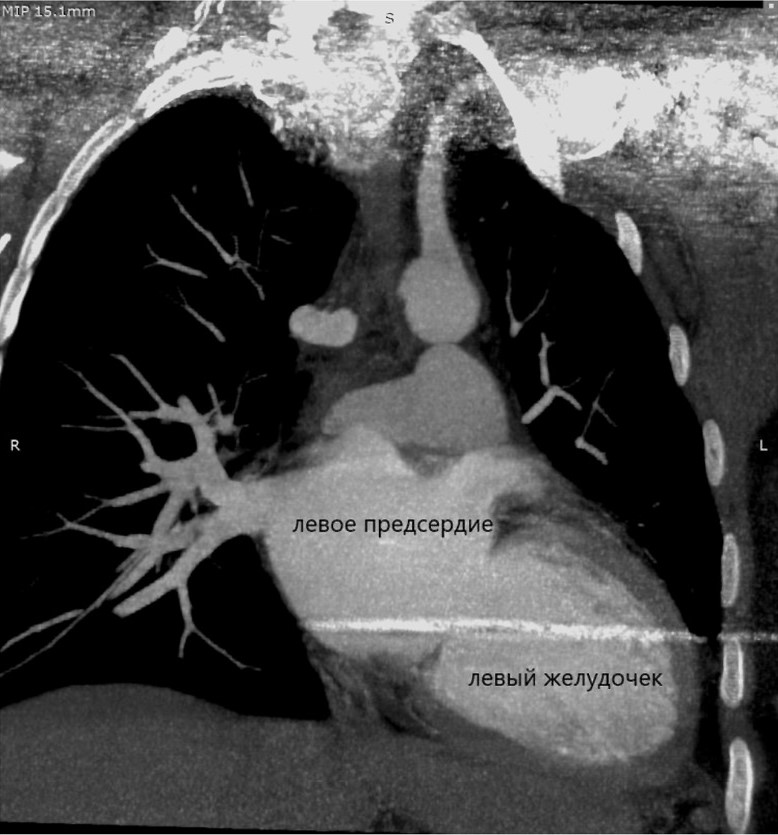

Рис. 4. Компьютерная томограмма пациентки К. Дилатация левых отделов сердца, пристеночные тромботические отложения в полости левого желудочка.

Fig. 4. Computed tomography of patient K. Left heart dilatation, wall thrombotic deposits in the left ventricular cavity.

Обращает на себя внимание выраженная задержка контраста в венах правой верхней конечности, куда вводилось контрастное вещество. Имеется богатая ветвь венозных анастомозов в мягких тканях грудной клетки, паравертебрально. ВПВ уменьшена в диаметре, её просвет практически полностью заполнен тромботическими массами от уровня впадения левой подключичной вены до места впадения непарной вены, сохранён просвет в виде узкой (1×4 мм) полулунной щели вдоль электрода. Непарная вена расширена, имеет диаметр до 10 мм и практически полностью обеспечивает верхний приток крови к правому предсердию. Основное возвращение крови к сердцу происходит через нижнюю полую вену, заполнение контрастом которой заметно отсрочено. Заключение: картина тромбоза/субтотальной облитерации ВПВ с организацией коллатерального венозного кровотока. Состояние после установки электрокардиостимулятора (ЭКС). Дилатация левых отделов сердца.